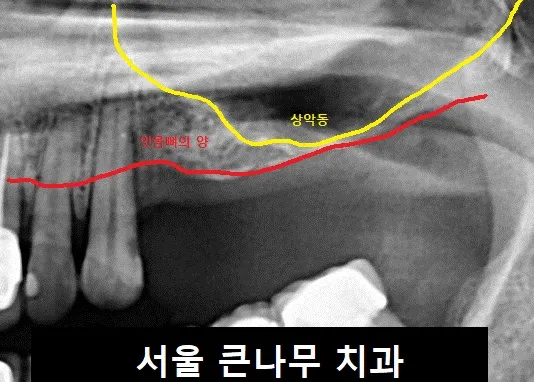

서울큰나무치과에 방문해 주신 40대 여성분입니다.

잇몸뼈가 한눈에 봐도 매우 얇은 모습입니다.

수술 전 CBCT를 찍어 한 번 더 확인하였습니다.

수술 뒤 CT사진을 찍어 확인하였습니다. 빨간 화살표만큼의 공간이 생겼습니다.

매우 얇았던 공간을 뼈이식을 해줌으로써 충분히 메꿔주었습니다. 이로써 상악동거상술의 과정이 끝나게 됩니다.